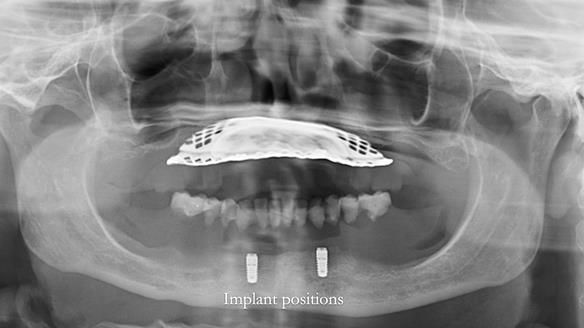

In this edition, I present the complete denture treatment for Kate, a 69-year-old American woman living in Garstang, UK. Kate had been edentulous for many years and required a set of complete dentures that closely mimicked her natural teeth. The new upper and lower dentures provided excellent retention and stability, with significant suction in the upper denture. Below, I detail the step-by-step process of her treatment, as well as my workflow for implant-supported overdentures for patients who may require them.

Kate had previously undergone treatment for Stage T3 breast cancer, which included three rounds of six-monthly bisphosphonate IV infusions. As a result, dental implants were not a viable option due to the high risk of MRONJ (medication-related osteonecrosis of the jaw), despite Kate having saved up money for implant-supported teeth. She was referred to me to deliver technically excellent dentures. Interestingly this case on my teaching website attracted her to the practice.